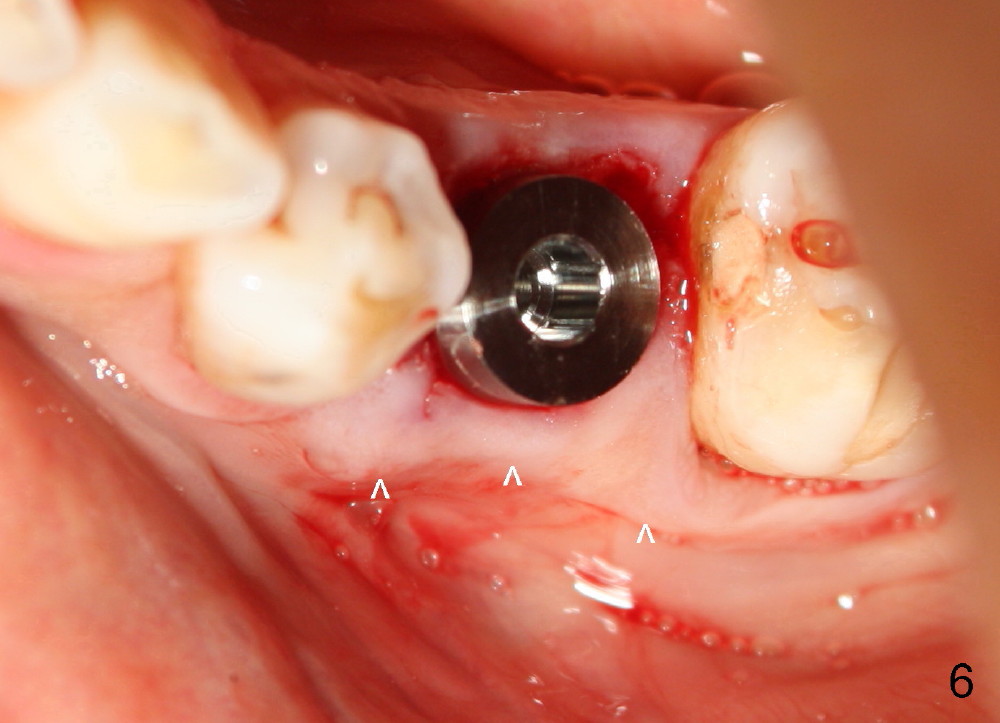

Taking multiple intraop X-ray is also necessary for depth adjustment (Fig.3-5). For example, when a 5x20 mm tap is inserted at the depth of 17 mm, it is close to the mental loop (Fig.4), whereas the binding to the bone is minimal. So a larger implant is to be placed at a shallower depth (Fig.5: 6x17 mm with insertion torque >60 Ncm). The shallower implant placement creates limited space for future abutment and crown (Fig.6,7). A short abutment will be used and the implant margin will be prepared as low as possible. As expected, the wound heals in a week (Fig.8).

Six months postop, bone density around the implant increases (Fig.9). There is slight gingival recession buccal to the implant (Fig.10 arrow). A short abutment is placed and prepared short (Fig.11 A); the margin is prepared as low as possible in the implant (I).